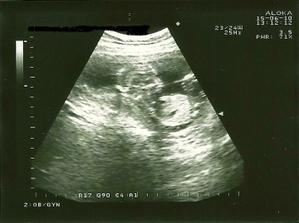

_1.6.2010 - sono v 14tt, NT ok, meriame 62mm 🙂 plus odber krvi